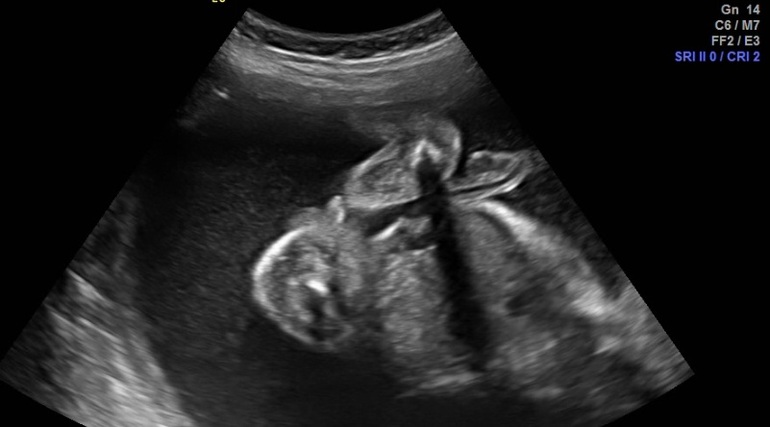

Посмотрите,кто по вашему ?

Пол малыша

на втором фото это могут быть половые губы ? если увеличить,то похоже. а сбоку что тогда ? но и на краник не особо похоже,както он сильно сбоку и вроде как отдельн.

У когото было похожее фото ?

Я, не чего понять не могу. На втором фоте, что то торчит, мальчик наверно.

На последней ракурс не до пола)))А на первой животик с органами и вроде как тоже ракурс не для пола,на второй мальчик